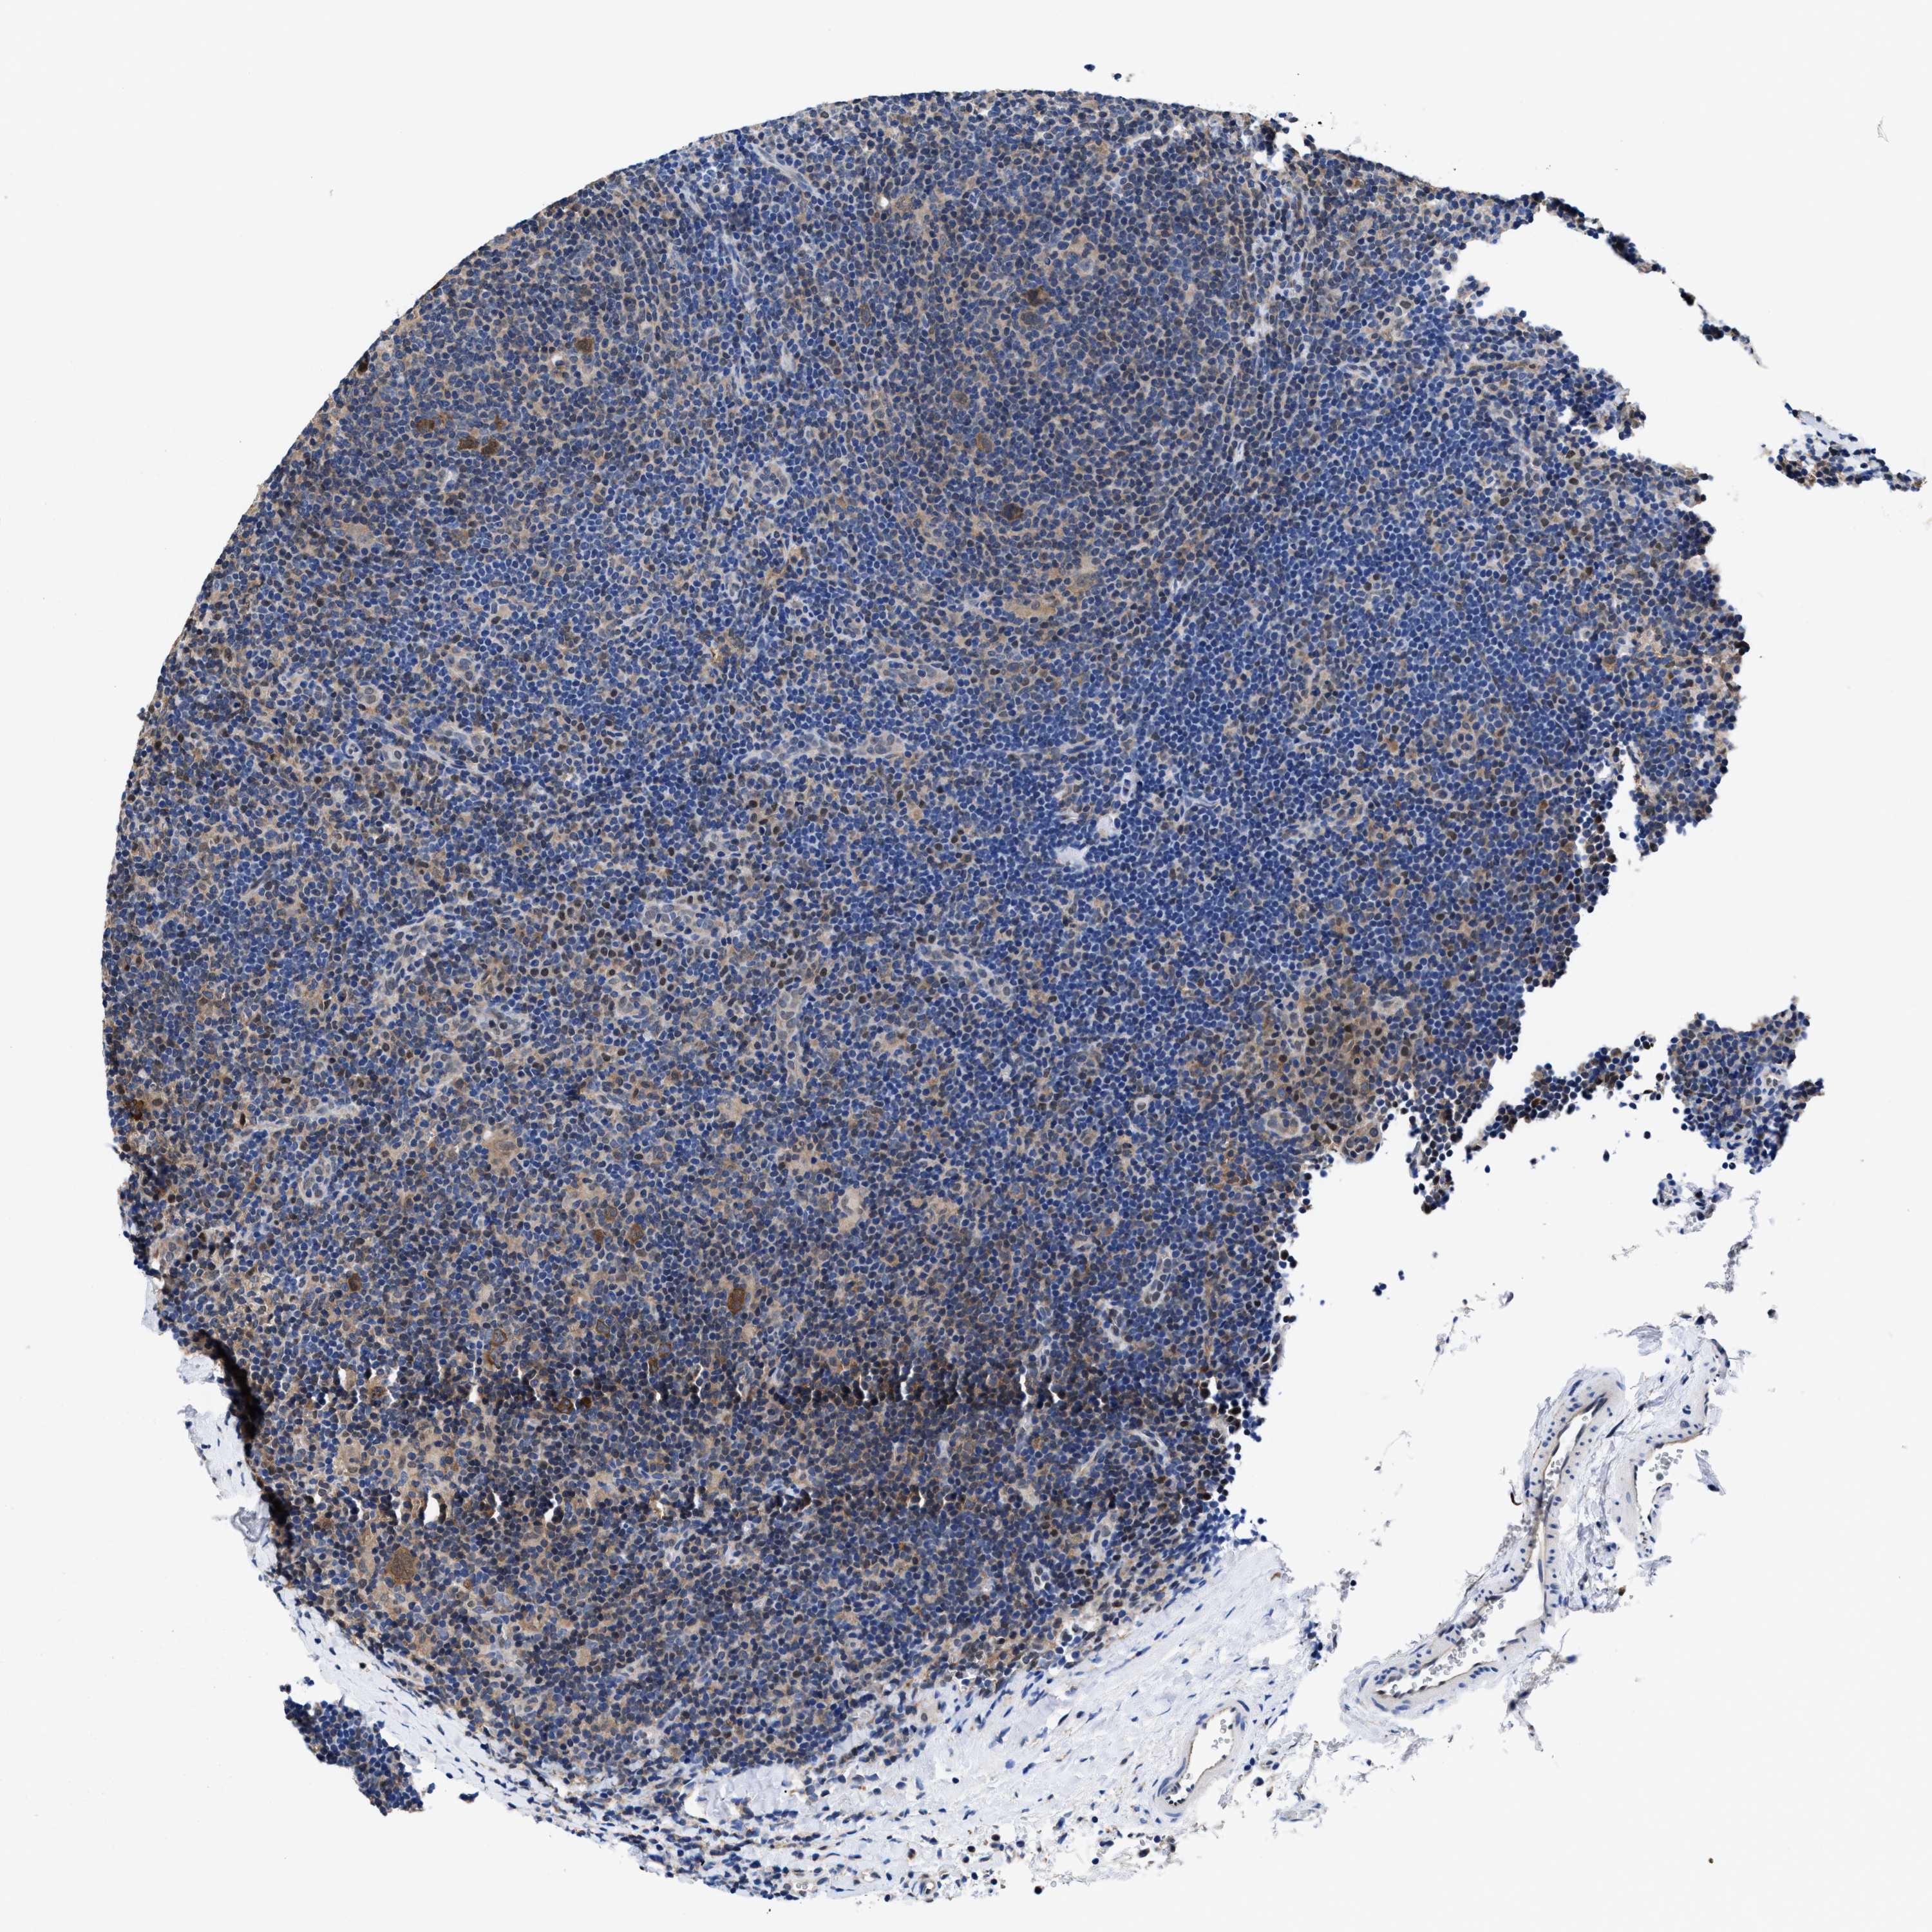

CANCER LYMPHOMA Show tissue menu

LYMPHOMA - Protein expressioni

A mouse-over function shows sample information and annotation data. Click on an image to view it in a full screen mode. Samples can be filtered based on level of antibody staining by selecting one or several of the following categories: high, medium, low and not detected. The assay and annotation is described here.

Antibody stainingi

Antibody staining in the annotated cell types in the current human tissue is reported as not detected, low, medium, or high, based on conventional immunohistochemistry profiling in selected tissues. This score is based on the combination of the staining intensity and fraction of stained cells.

Each image is clickable and will lead to virtual microscopy that enables deeper exploration of all samples and also displays staining intensity scores, fraction scores and subcellular localization as well as patient and tissue information for each sample.

HPA022434

HPA022953

HPA022959

HPA028758

CAB007783

Hodgkin's disease, NOS

Malignant lymphoma, non-Hodgkin's type, High grade

Malignant lymphoma, non-Hodgkin's type, Low grade